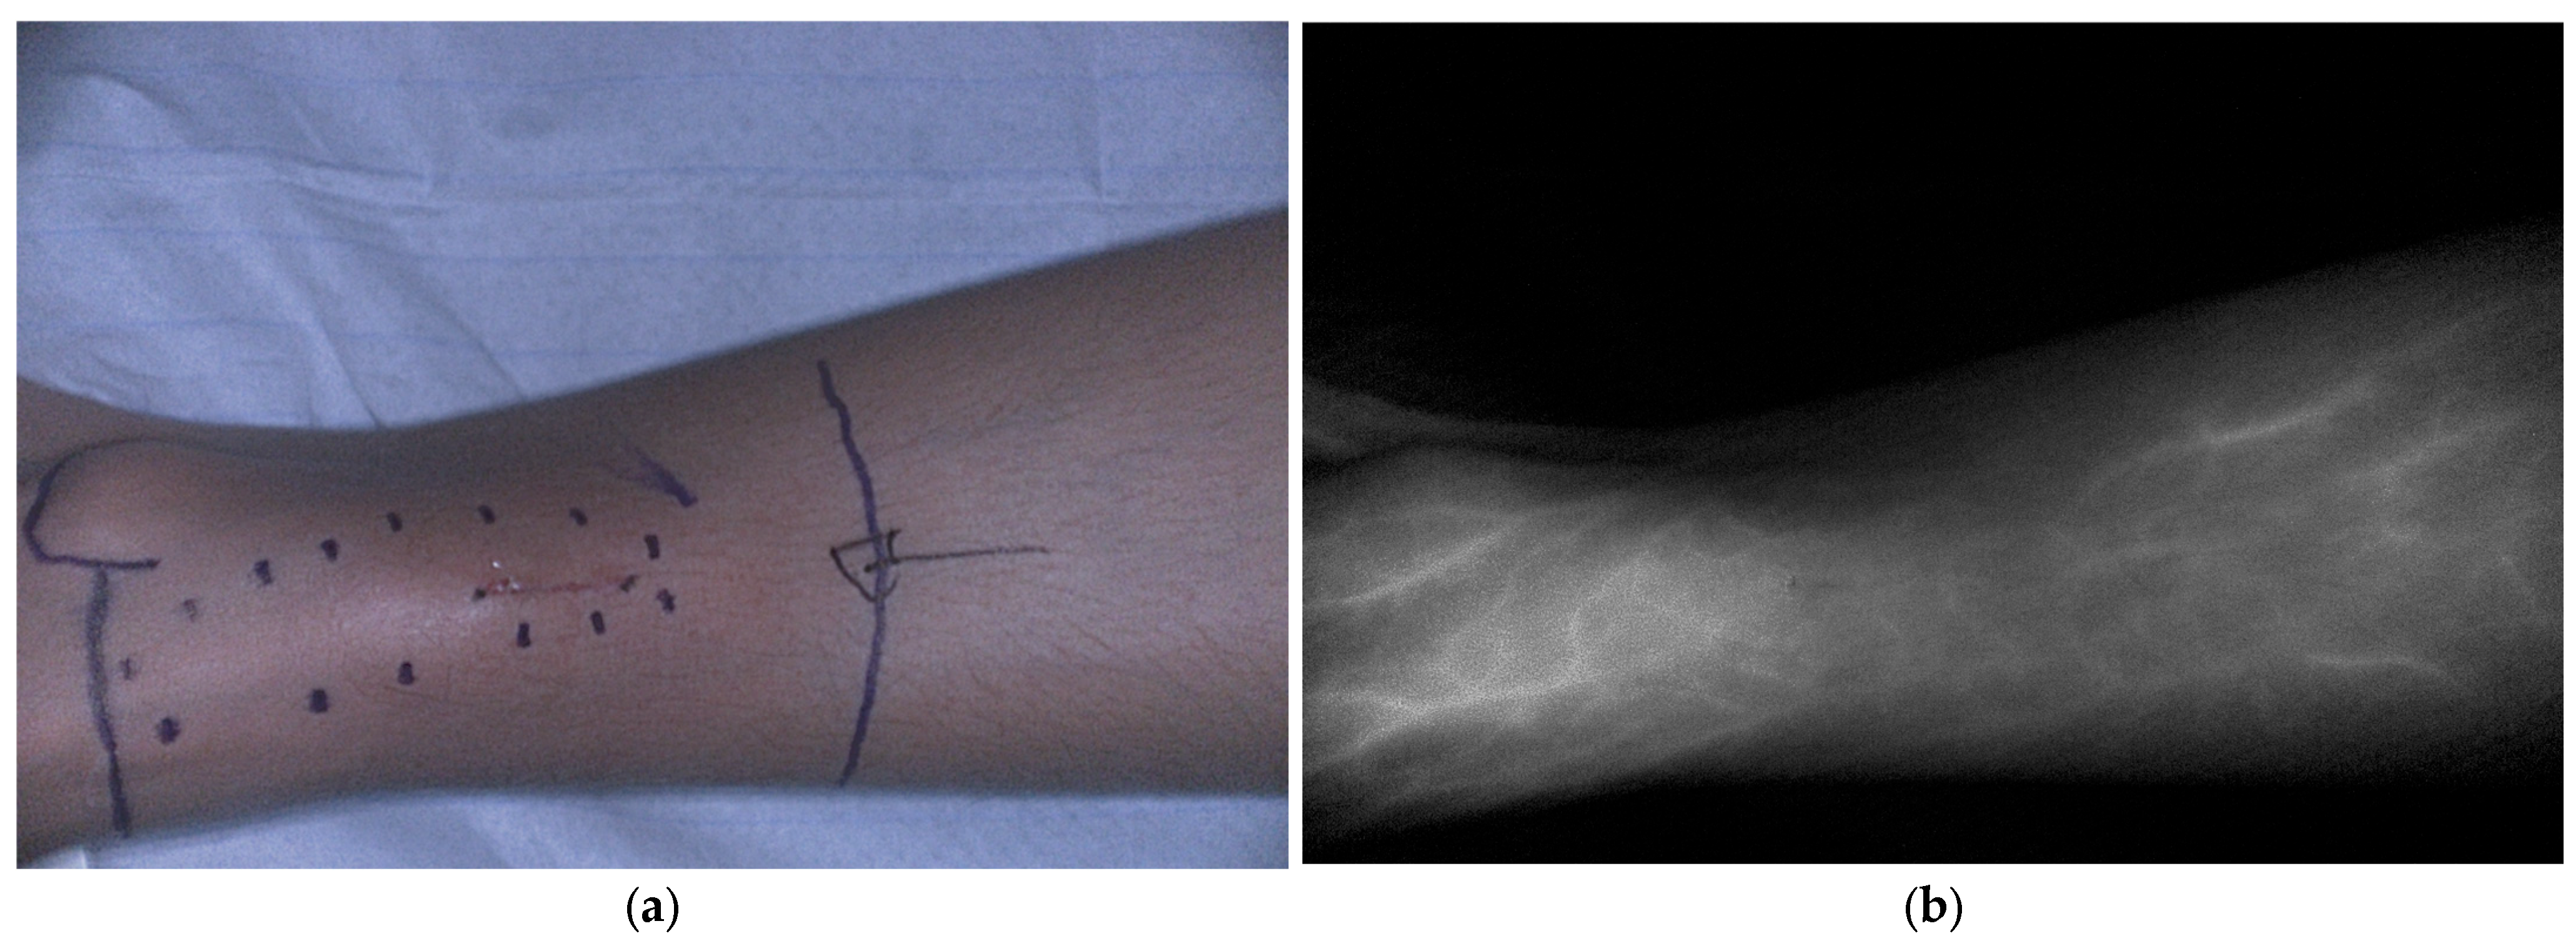

5.1.4. Bone and Soft Tissue Sarcoma

- Brookes, M.J.; Chan, C.D.; Crowley, T.P.; Ragbir, M.; Ghosh, K.M.; Beckingsale, T.; Rankin, K.S. Intraoperative Near-Infrared Fluorescence Guided Surgery Using Indocyanine Green (ICG) May Aid the Surgical Removal of Benign Bone and Soft Tissue Tumours. Surg. Oncol. 2024, 55, 102091. [Google Scholar] [CrossRef]

- Wang, H.; Ji, T.; Qu, H.; Yan, T.; Li, D.; Yang, R.; Tang, X.; Guo, W. Indocyanine Green Fluorescence Imaging May Detect Tumour Residuals during Surgery for Bone and Soft-Tissue Tumours. Bone Jt. J. 2023, 105-B, 551–558. [Google Scholar] [CrossRef] [PubMed]

| Clinical | Pediatric and young adults | Bone and soft tissue sarcoma | Guiding resection margins, identification of residual, and metastatic lesions | ICG 0.5–2.5 mg/kg 24 h before surgery | [36,37,38,39,40,41] | |